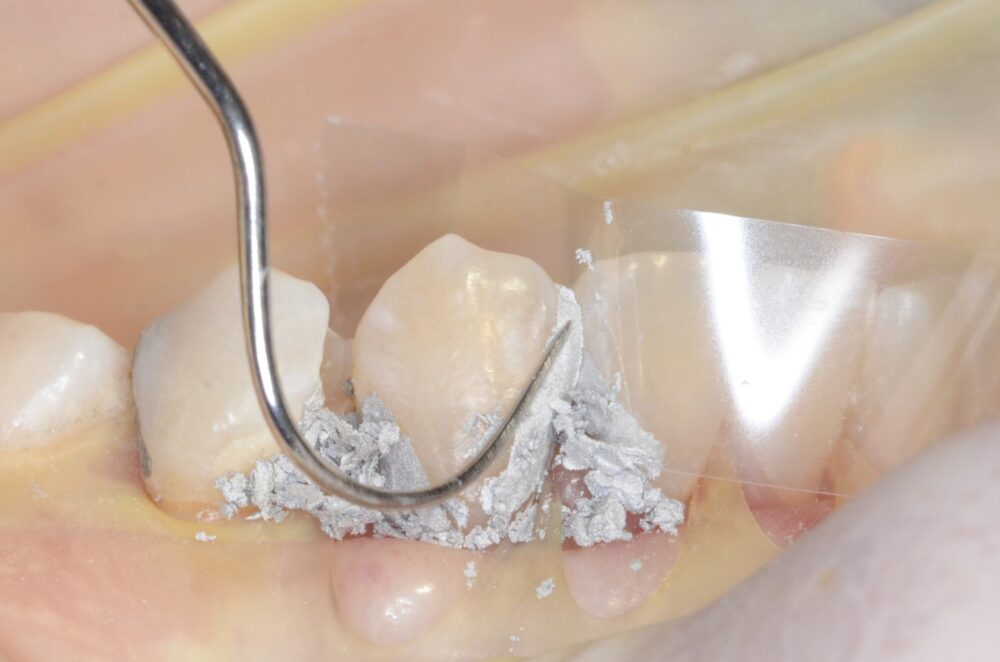

例えば、虫歯がひどく単に充填するだけでは歯の強度を元に戻すのが難しい歯の場合ピンを使います。

下の写真のようにピンを打って支えを作った歯にアマルガムを充填し、そのアマルガムを残したまま、ゴールド修復を行い、歯を被せることによって、強度を取り戻した歯にすることができます。

これらの治療は神経を刺激しない位置にチタン製でできたピンを打ち込まねばならず非常に神経を使う仕事です。